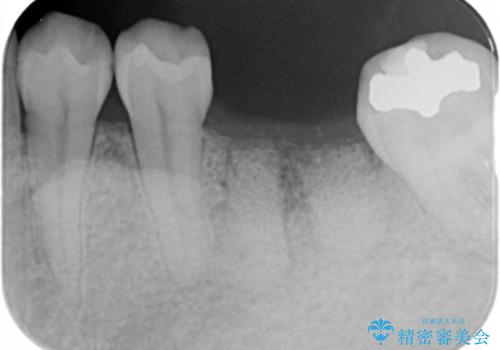

失った奥歯をインプラントで機能回復

- 失った歯の機能回復を希望され来院されました。

取り外しの必要な入れ歯、隣の歯を削る必要のあるブリッジに心理的抵抗があり、インプラントを用いて咬合機能を回復していくこととなりました。

元あった歯のようにしっかりと咬合機能が回復することができました。